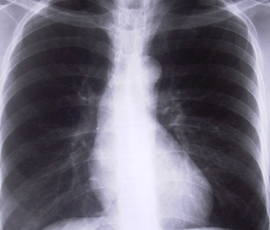

Lung cancer is the second most commonly diagnosed cancer in the UK after breast cancer, with 42,000 new cases in 2010. Survival rates in the UK are distressingly low and worse than across much of Europe – less than 10 per cent of patients are still alive five years after diagnosis.